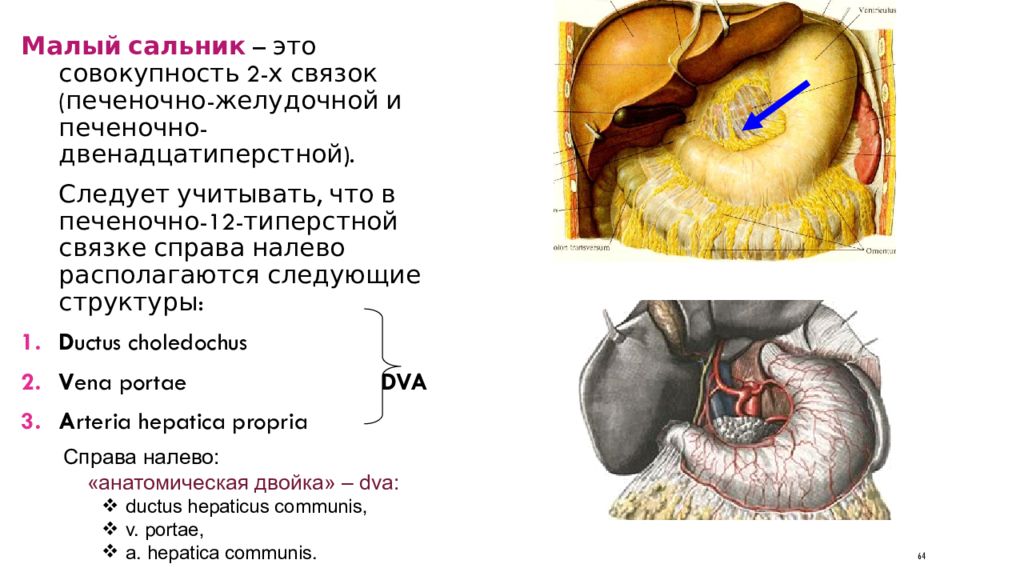

Анатомия и особенности Гартманова кармана желчного пузыря